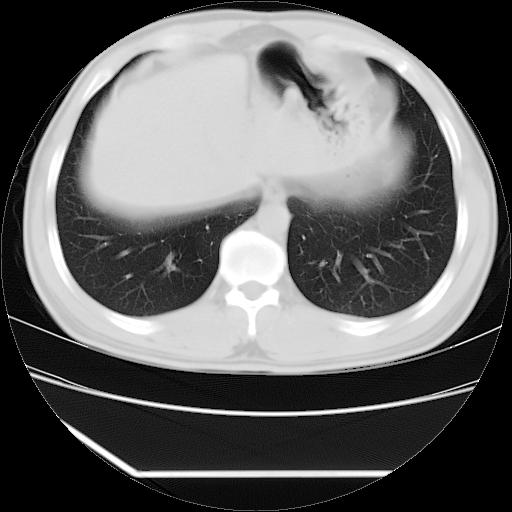

男,38岁,于2009年8月9日晚突发左侧胸痛,今x线提示左下肺阴影,为了明显确诊断,行ct检查,

血常规:嗜酸性细胞增高,单核细胞增高。

病灶发生在下叶,密度均匀,边缘模糊、毛糙,周围血管纹理增强扭曲改变,靠近胸膜处病灶胸膜反应明显。

支持考虑---球形肺炎。

左肺舌叶病变。主体病灶呈类圆形中心密度低,成液化趋势周边班片影分布

考虑肺脓肿

虽然实验室检查支持炎性病变,且病变内有坏死改变(中央呈大片状低密度影),但仍不能掉以轻心,鳞癌也可以有这种影像改变。